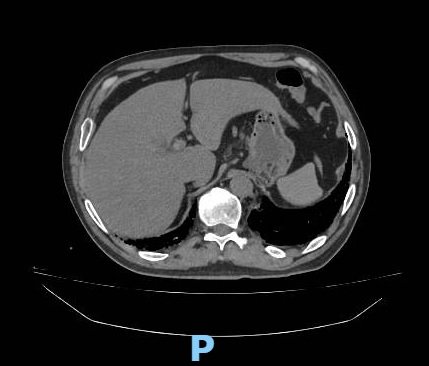

TC de abdomen sin contraste

Bazo y páncreas de forma y tamaño conservados, sin lesiones focales.